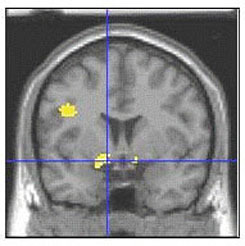

Social phobia, also called social anxiety disorder, is diagnosed when people become overwhelmingly anxious and excessively self-conscious in everyday social situations.

Social phobia affects about 15 million American adults. Women and men are equally likely to develop the disorder, which usually begins in childhood or early adolescence. There is some evidence that genetic factors are involved. Social phobia is often accompanied by other anxiety disorders or depression,and substance abuse may develop if people try to self-medicate their anxiety.